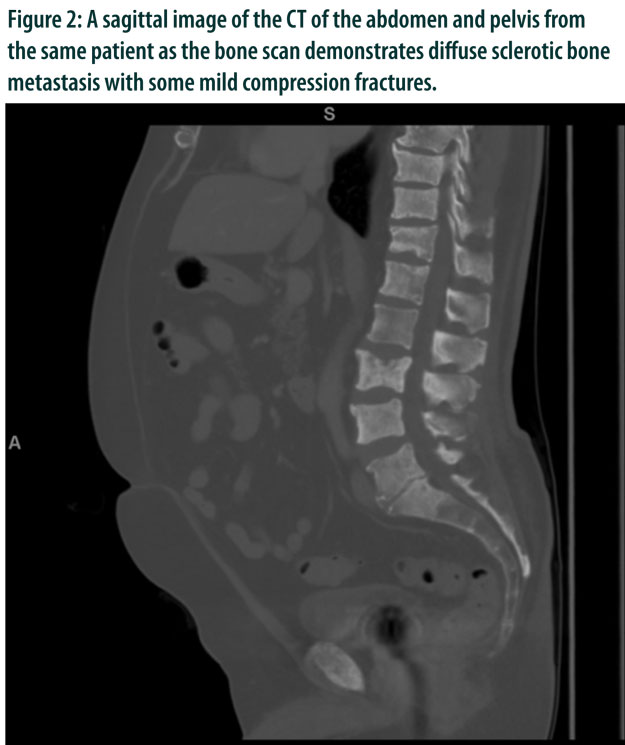

Prostate Cancer Imaging: Ultrasound, CT, MRI, and Nuclear Medicine Techniques